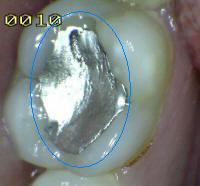

4 |

Amálgama |